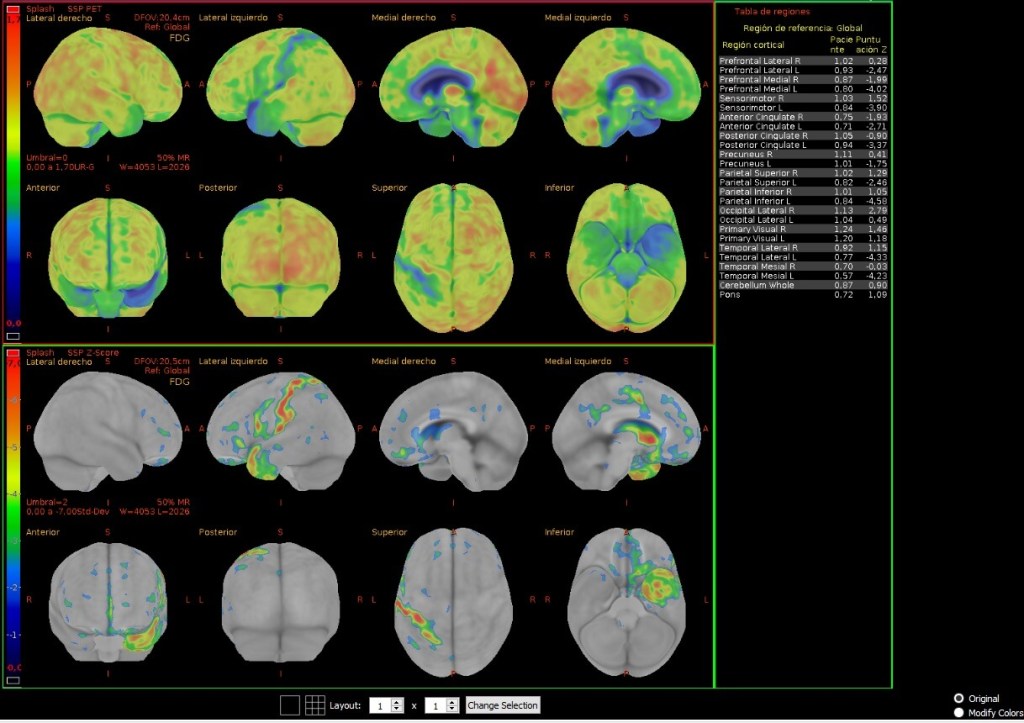

El resultado es un mapa funcional del cuerpo: no muestra lo que está ahí, sino lo que está ocurriendo. Por eso, la PET es tan eficaz para detectar tumores, comprobar la eficacia del tratamiento o valorar si quedan restos tumorales tras una intervención. Y no solo eso: también permite anticiparse a enfermedades neurológicas como el Alzheimer o el Parkinson, mostrando alteraciones cerebrales antes incluso de que aparezcan los primeros síntomas. En el corazón, ayuda a identificar zonas dañadas tras un infarto o problemas en el flujo sanguíneo. Y en investigación, ha abierto puertas para comprender cómo se comporta el cerebro en trastornos psiquiátricos, epilepsia o depresión.

Y la inteligencia artificial ya ha empezado a transformar este campo. Gracias al análisis automatizado de imágenes, es posible detectar patrones invisibles al ojo humano, anticipar diagnósticos y personalizar tratamientos de forma cada vez más precisa.